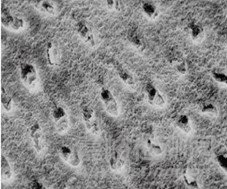

采用牙科用磷酸酸蝕劑對牙釉質(zhì)表面進(jìn)行酸蝕處理,可清除釉質(zhì)表面的涎液沉積物、菌斑及其他附著物,使表面羥基磷灰石礦物質(zhì)不均勻脫礦,形成凹凸不平的蜂窩狀表面結(jié)構(gòu),見圖1。這種結(jié)構(gòu)不但增加了粘接的表面積,而且能夠使粘接劑與釉質(zhì)間形成微機(jī)械嵌合作用,產(chǎn)生牢固的結(jié)合力。

圖1 牙釉質(zhì)表面酸蝕前后形態(tài)掃描電鏡圖示例

如圖1所示,(左)酸蝕前,正常的牙釉質(zhì)表面致密;(右)酸蝕后,表面不均勻脫礦,呈現(xiàn)蜂窩狀結(jié)構(gòu)。